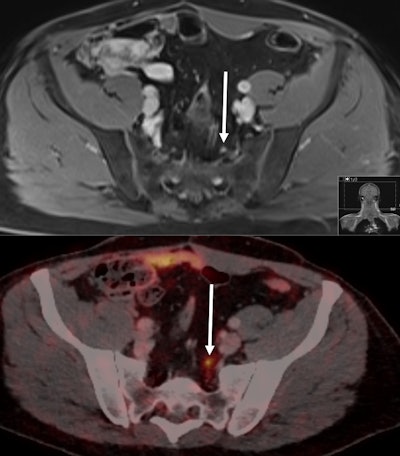

Images from a 55-year-old patient with biochemical recurrence of prostate cancer following radical prostatectomy four years previously. His PSA rose to 0.51 ng/mL at the time of imaging. PSMA-PET CT (bottom) identified a 5-mm small lymph node metastasis due to the pathologic PSMA uptake in the left presacral region (maximum standardized update value of 6.1). The lymph node was falsely rated as nonmalignant on MRI based on its small size and ovoid shape. Images courtesy of Sawicki et al.Head-to-head comparison